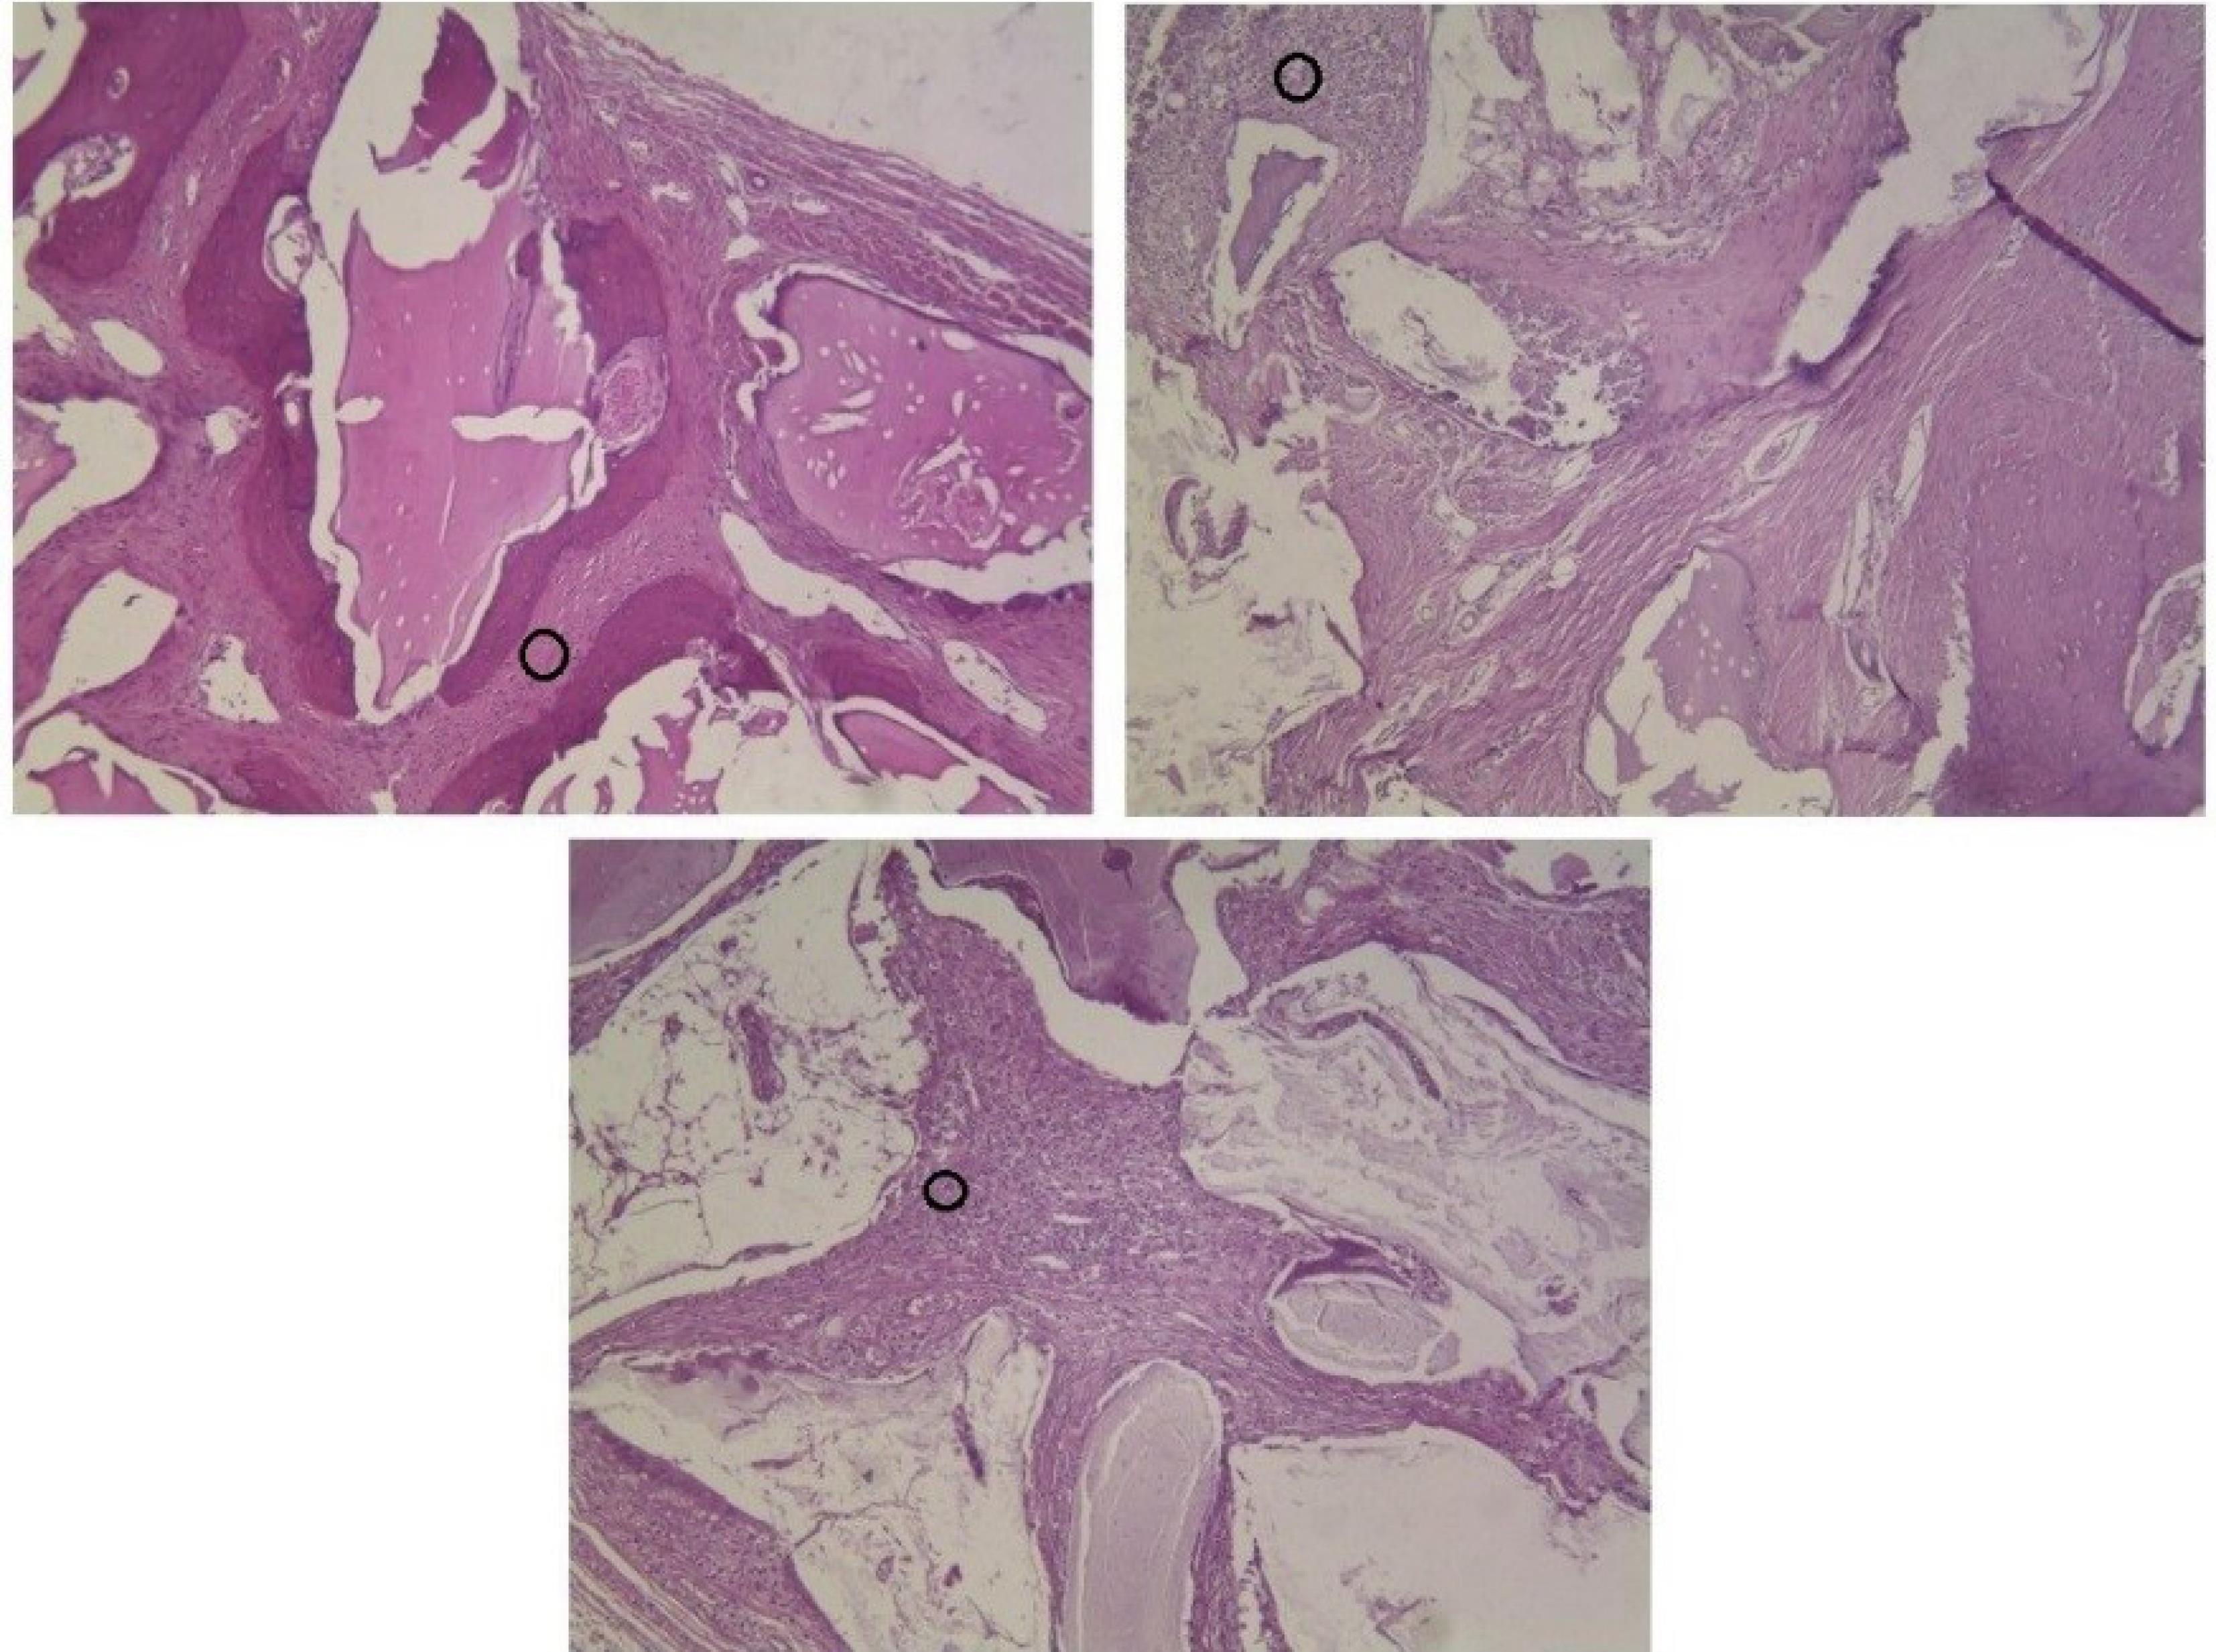

The majority of defects showed foreign body reactions after 8 and 12 weeks. Foreign body reaction is induced by special cells called multi-nucleated giant cells (MNGCs) that result from the fusion of macrophages. Despite older statements, recent studies indicated that the presence of MNGCs around bone materials was a favorable finding because these cells were capable enough to express growth factors and angiogenic cytokines such as vascular endothelial growth factor (VEGF) and further stimulate bone formation and tissue healing.28,29 Based on these reports, the presence of MNGCs in the present study could be a positive finding and may have induced osteoblastic function and further osteogenesis. Figure 8 shows the presence of MNGCs around xenografts in different groups.

Figure 8.

Black circles show aggregation of giant cells around different xenografts